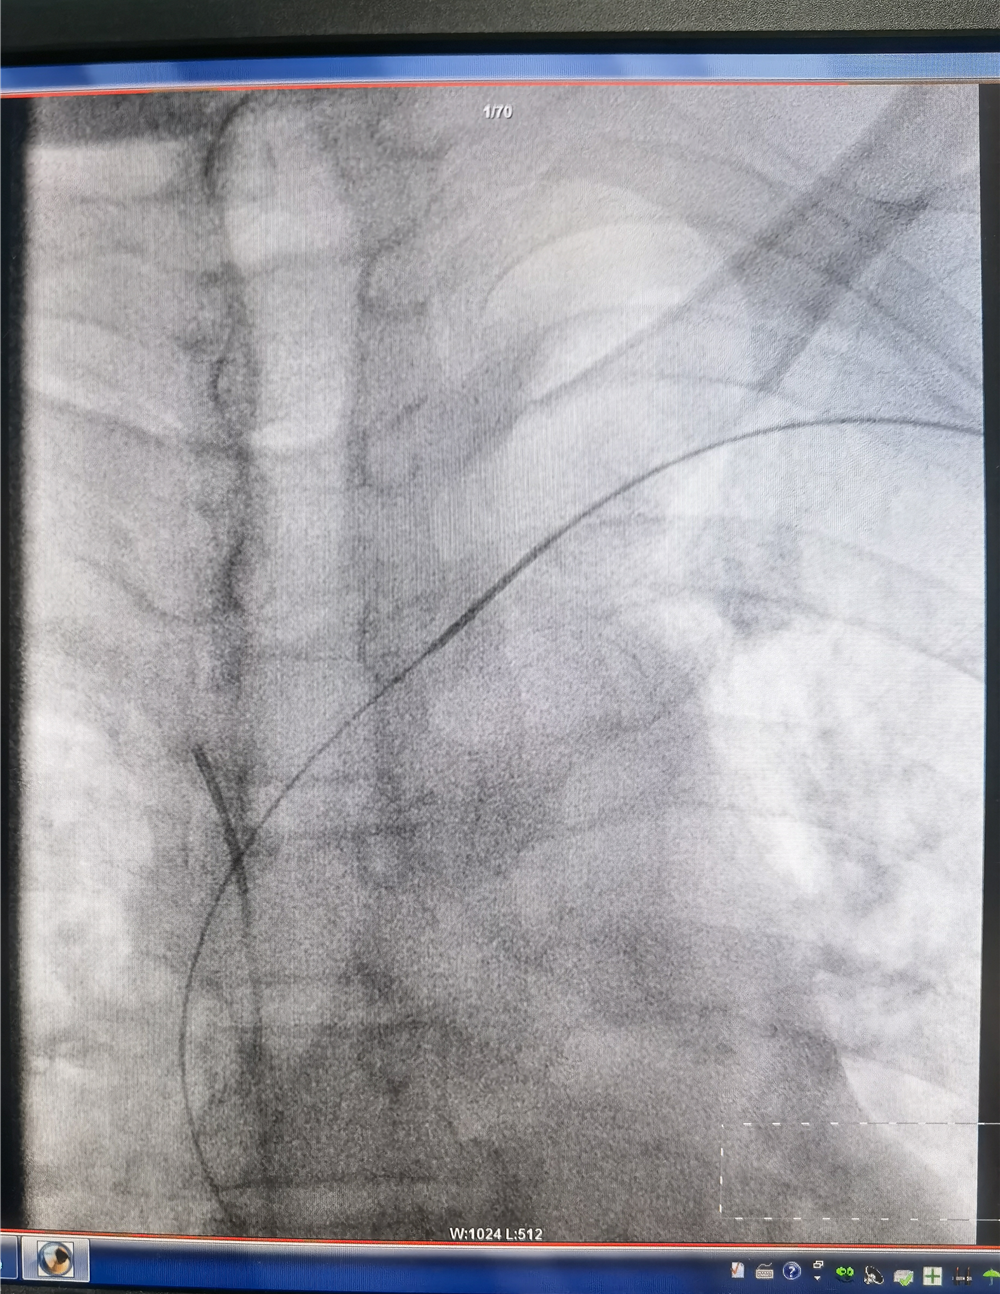

今天上午,我科刘政主任、张玉冬副主任医师、王冠主治医师会同肾病科靖永胜主任共同为田大爷进行了左头臂静脉球囊扩张成形术。术中发现患者左侧头臂静脉完全闭塞,导丝与导管正向通过阻力很大。

遂取同侧股静脉入路,将导管置于上腔静脉,造影未能显示头臂静脉汇入口,留置导管作为标记,更换加硬导丝支撑,从上肢入路顺利通过闭塞段进入上腔静脉。